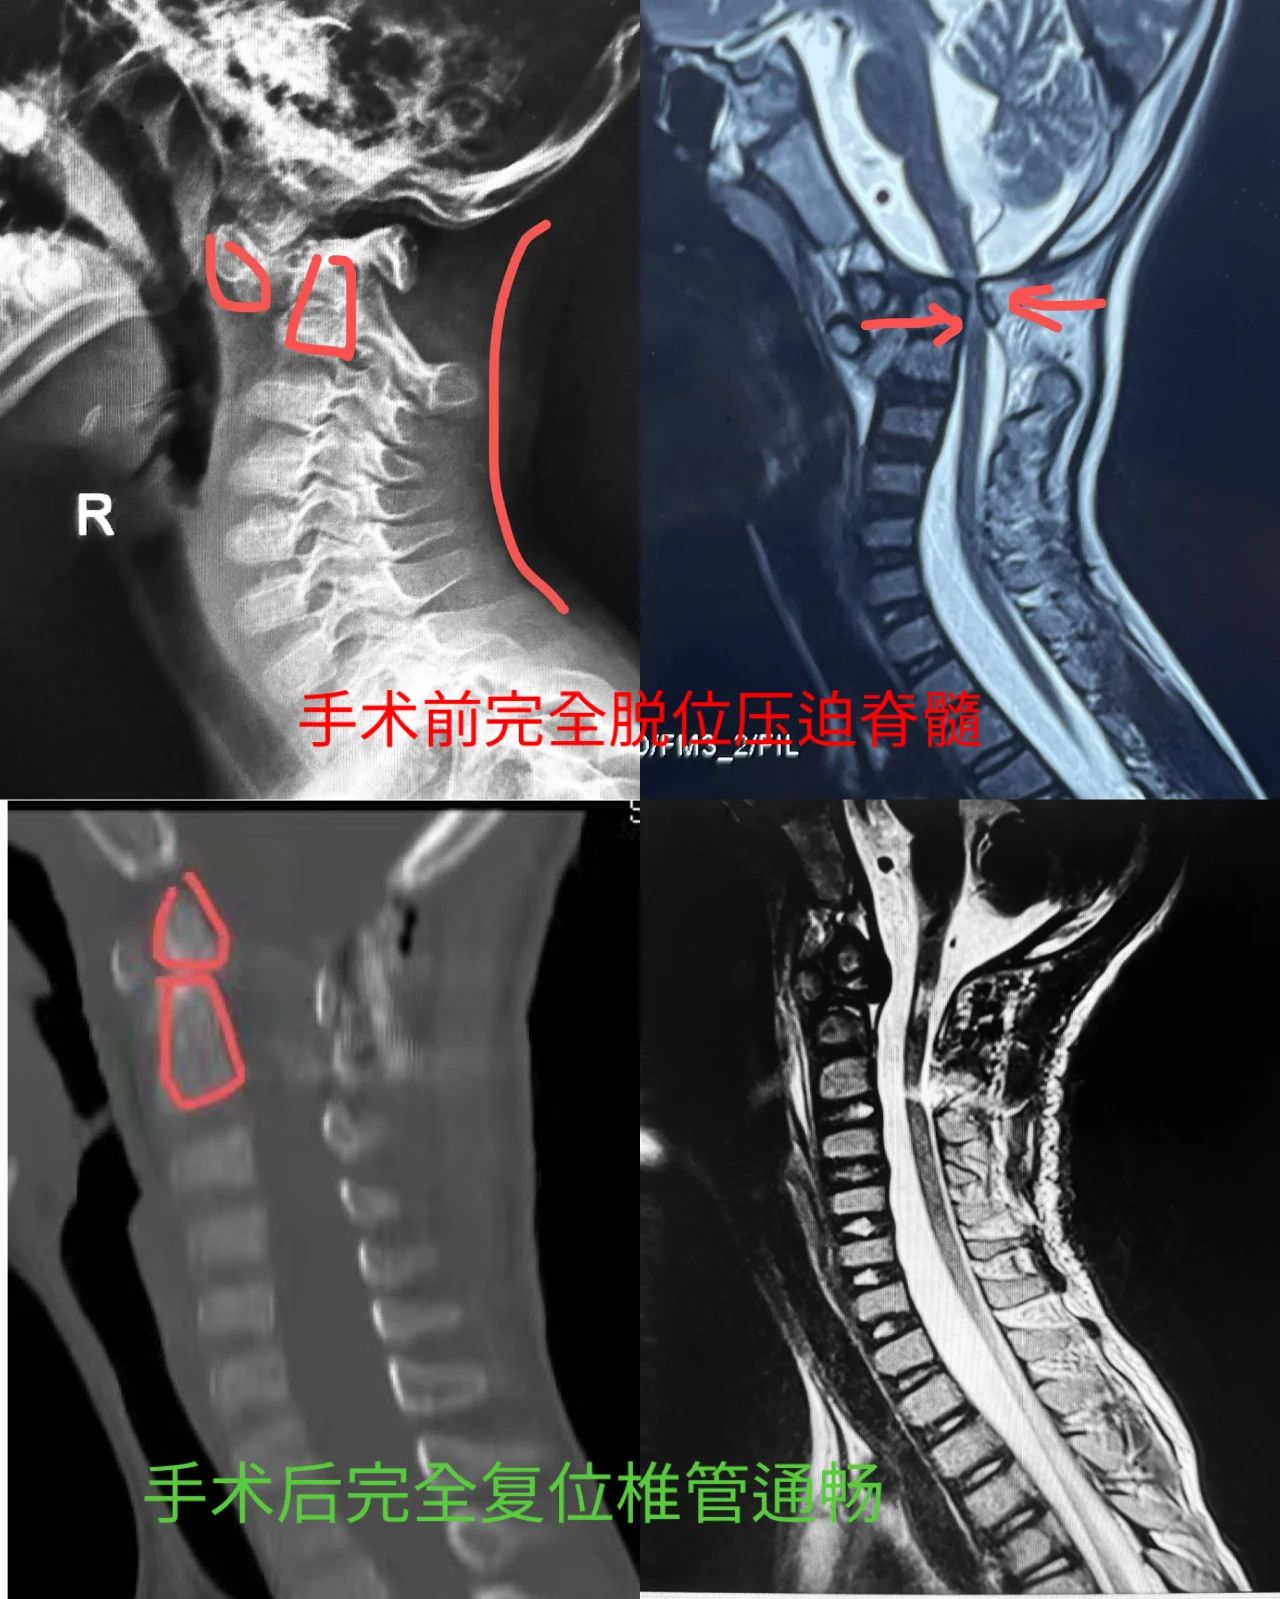

上周,小斌父母推着轮椅上的他,来到我院骨科与运动医学中心再次找徐杰教授。徐杰接诊后,综合病史与影像检查,孩子这是颈椎的寰枢椎完全脱位,即寰椎关节脱位到枢椎关节前方,发生了交锁并压迫到脊髓神经了。

寰枢椎全脱位,指的是颈椎的第一节寰椎与第二节枢椎之间的关节失去了正常对合关系。单从颈椎CT上看,这位严重寰枢椎脱位的患者象是成了“断头人”。更糟的是,原本穿行在椎管间的重要脊髓神经被严重卡住,这里就是在呼吸中枢附近,若病情拖延,脊髓神经会缺血坏死,导致患者不可逆的高位截瘫、呼吸衰竭等,进而威胁生命。

针对这一特殊的病例,徐杰教授、肖毓华副主任医师、俞云龙博士、余博飞医师团队研究制定了一整套确保手术安全成功的新方案新流程。手术取俯卧位,徐杰教授与肖毓华副主任医师使用脊柱手术显微镜,采取一种新的复位方法对交锁的寰枢侧块关节进行解锁复位并在畸形的寰椎精准打入了4枚椎弓根钉子,复位满意后,手术中神经电生理监测显示脊髓神经反应良好。

手术后,小斌的高位截瘫恢复,四肢又能控制活动了,手术后第二天下床练习走路。